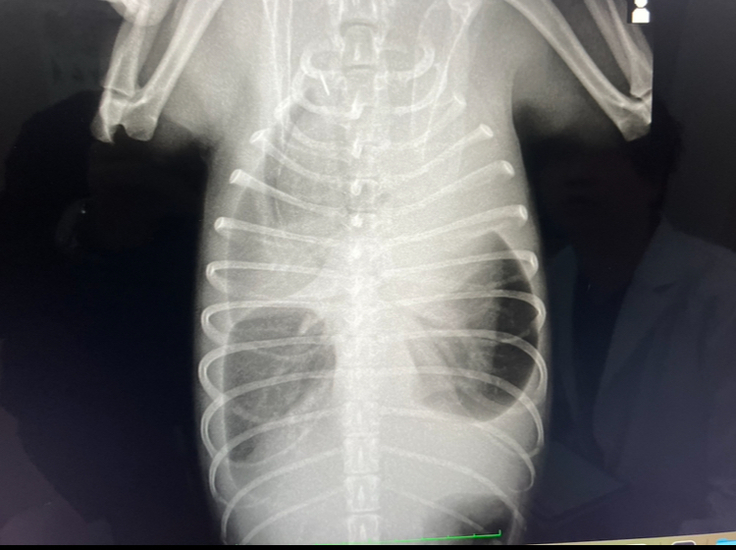

レントゲンを撮影した所、肺が真っ白に、、特に左前の肺は殆ど写っていませんでした。

すぐに特定はできなかったものの動物病院に一旦お預けして調べを進めていただいた所、「乳び胸(にゅうびきょう)」である可能性が極めて高い事がわかりました。

みかんの胸には約350ccもの乳びが溜まっていて呼吸を圧迫していました。